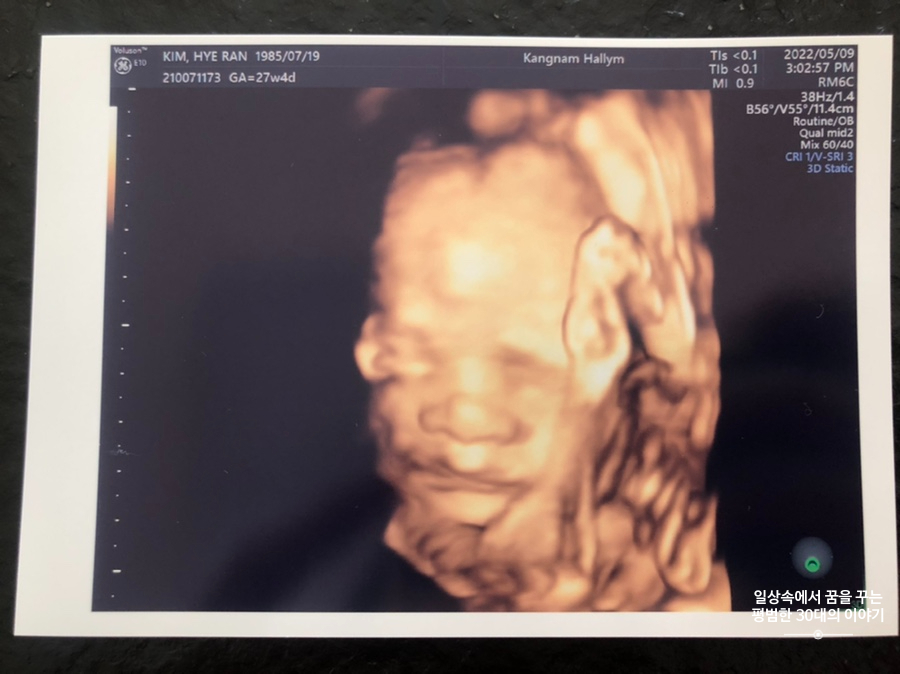

5월 9일 월요일(27주차 4일)

BPD(Biparietal Diameter, 위에서 볼 때 태아 머리 단면의 가장 긴 길이): 6.93cm

HC(Head Circumference, 태아 머리둘레): 25.78cm

AC(Abdominal Circumference, 배 둘레): 23.84cm

EDD(Expected Date of Delivery, 출산 예정일): 2022년 8월 4일

FL(Femur Length, 허벅지뼈 길이): 5.08cm

GA(Gestational Age, 임신 주차): 27주차 4일

EFW(Estimated Fatal Weight, 태아 예상 체중)=EBW(Estimated Body Weight): 1138g

FHR(Fetal Heart Rate, 심장박동 수): 165bpm

CL(Cervical Length, 자궁경부 길이): 4cm

AF(Amniotic Fluid, 양수): 정상

오늘은 입체 초음파 보는 날!!! 입체 초음파는 처음인데다 3주 만에 이안이 얼굴을 본다 생각하니 무척 설레는 마음으로 병원에 갔다. 첫 번째 시도에서는 계속 내 등 쪽으로 얼굴을 대고 엎드려 있어 실패! 초코우유 먹고 열심히 걸은 후, 30분 뒤에 다시 진행한 두 번째 시도에서는 얼굴 반쪽을 보여줬다. 얼굴 전면을 보지 못해 너무 아쉬웠지만 그래도 손가락 빨고 있는 모습, 웃고 있는 모습, 입 뻐끔 거리는 모습, 발차기 하는 모습, 손가락 쥐었다 폈다 하는 모습, 손을 휘적휘적 거리는 모습 등 다양한 모습을 보여줘서 그것만으로도 충분히 만족스러웠다. 내가 다니고 있는 강남성심병원은 입체 초음파가 다른 병원에 비해 무척 비싼 편인데(진료비 내역을 보니 초음파 진단료가 129800원 나옴) 그나마 위안을 삼을 수 있는 것은 화질이 그나마 좋은 편이라는 것이다.